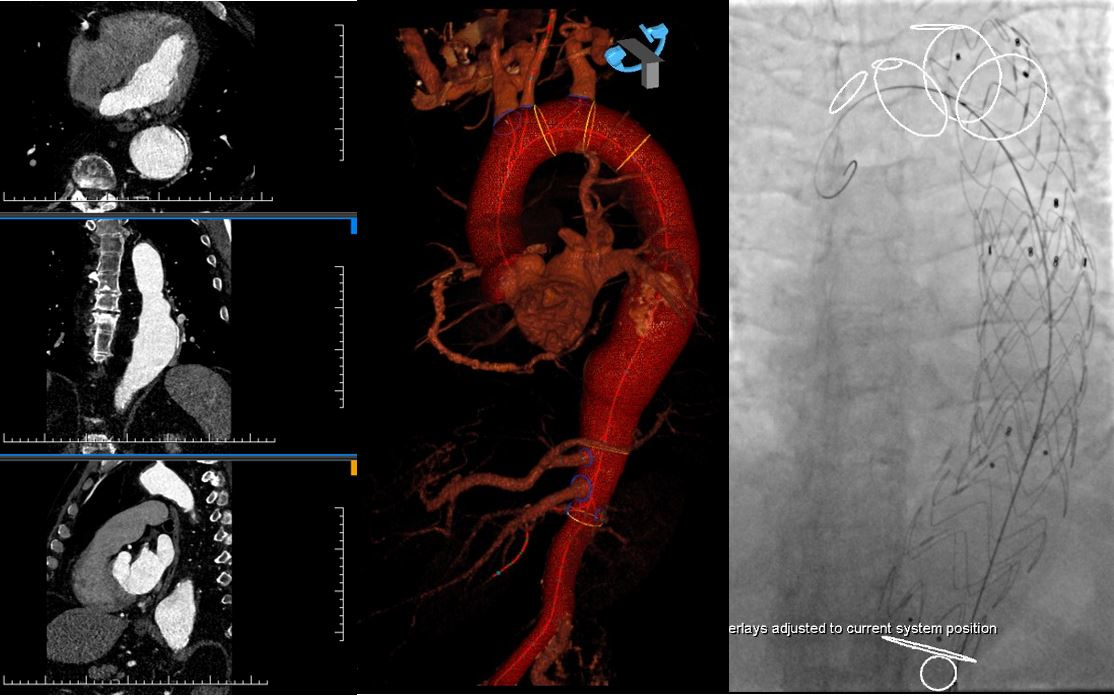

Stredoslovenský ústav srdcových a cievnych chorôb patrí k vedúcim centrám v endovaskulárnej liečbe výdutí a disekcií aorty na Slovensku. Prístroj vďaka integrovanému intravaskulárnemu ultrazvuku a najmodernejšiemu softwarovému vybaveniu, vrátane 2D/3D navigácie a fúzie s CT obrazom, ďalej posúva možnosti terapie a umožní bezpečnejšiu liečbu aj tých najkomplikovanejších prípadov.

Nový prístroj si našiel okamžité uplatnenie v liečbe komplexných ochorení aorty.

Pacient s objemnou výduťou hrudnej aorty s krátkou implantačnou zónou ošetrený za pomoci 3D navigácie hrudným stentgraftom a fixovaný pomocou endoskrutiek za účelom zabránenia neskorej migrácie (posunu) graftu.